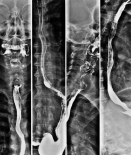

Während Sie den Kontrastmittelbrei (Bariumsulfat – Prontobario HD) schluckweise trinken, beobachtet der Radiologe unter Durchleuchtung am Monitor, wie das Kontrastmittel durch die Speiseröhre fließt. Anschließend wird in liegender Position überprüft, ob ein Rückfluss vom kontrastmittelgefüllten Magen zurück in die Speiseröhre erfolgt (sogenannte Refluxerkrankung).

Im Videoschluckakt kann speziell auch die Schleimhaut der Speiseröhre beurteilt und anhand der Videoaufzeichnung Schluckstörungen analysiert werden.